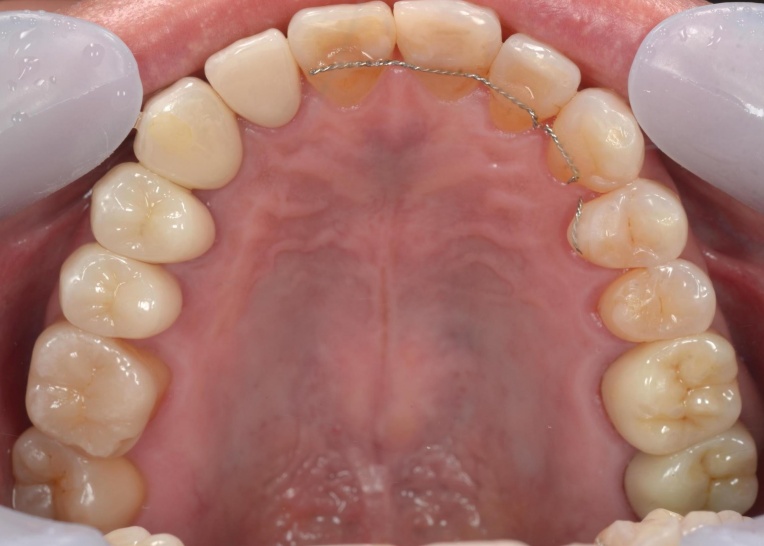

矯正治療終了後は、整えた歯並びが後戻りしないよう、細いワイヤーを固定して歯並びを安定させる装置「リテーナー」を装着しました。

その後、小樽山岡デンタルオフィスにてインプラント治療と被せ物の治療を行い、治療を終了しています。

治療前

治療後